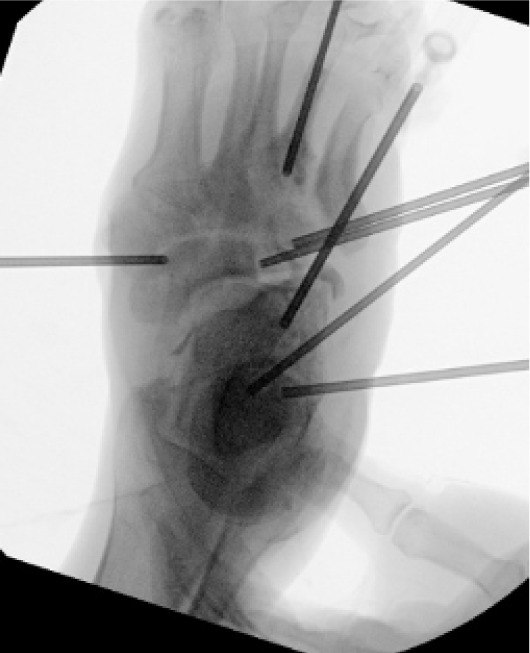

Two days after the initial debridement, the patient underwent corrective surgery to address the underlying structural deformity. Procedures included correction of metatarsus adductus, Lapidus bunionectomy, and application of an external fixator to stabilize the midfoot and offload the lateral column (Figure 2).

FIGURE 2 Postoperative photograph showing external fixator placement with midfoot realignment.